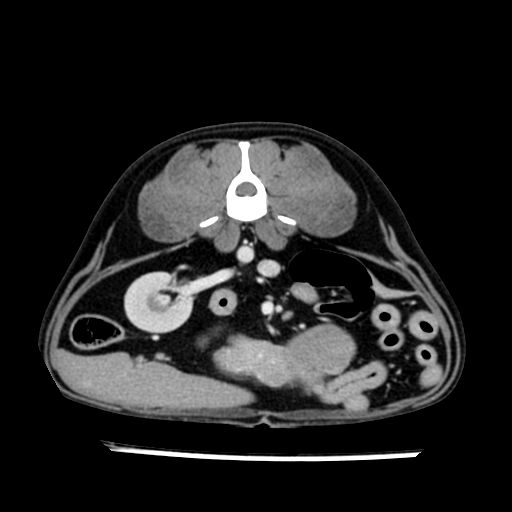

prescritto esame TAC

sequenza immagini limitata al fegato reni e surreni

le immagini ecografiche rispetto alla tac datano circa 7 mesi prima ,le surrenali sono normali nonostante il test acth sia risultato positivo .all’esame TAC dopo diversi mesi risultano aumentate armonicamente nel volume e si individua un forte sospetto di adenoma ipofisario .

sospetto adenoma ipofisario vs. meno probabilmente meningioma della base; intertiziopatia polmonare; lesione espansiva epatica, verosimilmente del lobo laterale sinistro, di sospetta natura neoplastica; lesioni spleniche di natura da definire; iperplasia/ipertrofia delle ghiandole surrenali, bilateralmente; vertebra di transizione del rachide toracico; tenosinovite cronica del muscolo bicipite brachiale di destra.

- l’esame tac e’ stato eseguito circa quattro mesi dopo la prima ecografia che non aveva messo in evidenza aumento del volume surrenalico (vedi immagini) ma solo la lesione epatica, la presenza di PU PD aveva portato ad un controllo per l’ ipercorticosurrenalismo confermato dal test act , in questo caso, si deduce che i sintomi di ipercorticosurrenalismo legati all’adenoma sono comparsi prima delle modificazioni surrenaliche, quindi in caso di sospetto ,a mio avviso e’ buona norma eseguire prima il test di stimolazione e dopo L’ECOGRAFIA per tentare una classificazione eziopatogenetica . La Tac si e’ quindi dimostrata molto valida in sensibilita’ e specificita’ riguardo la patologia surrenalica in quanto in grado di vedere o fortemente sospettare (ovviamente meno sensibile della RM) un piccolo adenoma ipofisario e le alterazioni morfovolumetriche della surrenale.